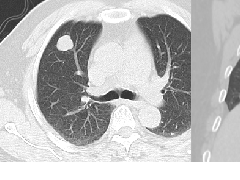

张力性纵隔气肿影像表现及严重度分级  迅速增大的肺部结节,首先考虑良性,确诊需要肺穿